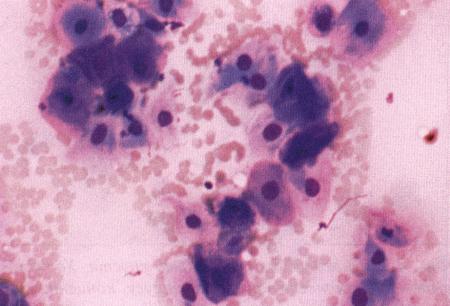

Фиг. 1.3.

Эндоскопическое исследование слизистой влагалища. Динамика изменений на протяжении цикла: (а) проэтрус — розовая окраска и отечность; (b) начало эструса — слизистая бледнеет, отек начинает уменьшаться (обычно перед пиком ЛГ); (c) середина эструса — слизистая бледная, уменьшение отека (сморщивание) явно выражено, что соответствует середине фертильного периода; (d) начало метэструса — видны закругленные складки, при прикосновении слизистая смыкается, образуя розетку (е) (см. Приложение)